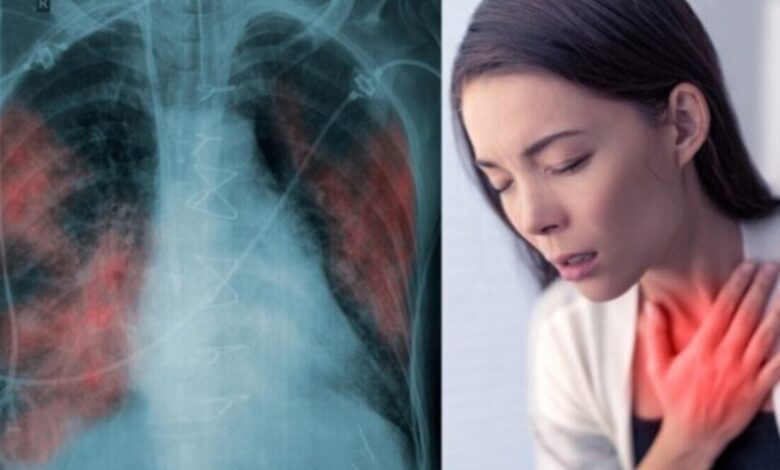

Stage 1 Lung Cancer की ओर इशारा करते हैं ये लक्षण, जानकर हो जाएं सावधान!

शरीर में ऑक्सीजन पहुंचाने और कार्बन डाइऑक्साइड को बाहर निकालने में फेफड़े मदद करते हैं। अगर आपके फेफड़े मजबूत हैं तो आपको सांस लेने में किसी भी तरह की दिक्कत महसूस नहीं होगी। लेकिन, अगर आपके फेफड़े कमजोर हो रहे हैं तो आपको सांस लेने में तकलीफ हो सकती है। आज के इस लेख में हम कुछ ऐसे कॉमन लक्षणों के बारे में जानकारी हासिल करेंगे, जो स्टेज 1 लंग कैंसर की तरफ इशारा करते हैं।

लगातार खांसी की समस्या को मामूली समझने की गलती आपकी सेहत पर भारी पड़ सकती है। स्टेज 1 लंग कैंसर के दौरान मरीज को सूखी खांसी हो सकती है। बता दें कि स्टेज 1 फेफड़े के कैंसर के लक्षण अक्सर हल्के होते हैं। कुछ मामलों में तो शुरुआती स्टेज में लक्षण महसूस ही नहीं होते हैं।

क्या आपको भी अक्सर सीने में हल्का दर्द या फिर भारीपन या फिर दबाव महसूस होता है? अगर हां, तो आपको इस तरह के लक्षण को मामूली गैस समझने की गलती नहीं करनी चाहिए। लंग कैंसर के दौरान भी इस तरह के लक्षण दिखाई दे सकते हैं। सांस लेने में दिक्कत महसूस होना या फिर सांस फूल जाना, इस तरह के लक्षण भी फेफड़े के कैंसर का संकेत साबित हो सकते हैं।

अगर आपको बार-बार ब्रोंकाइटिस या फिर निमोनिया की समस्या हो रही है, तो आपको जल्द से जल्द अपनी जांच करवा लेनी चाहिए। लंग कैंसर की वजह से आपको बार-बार इस तरह के रेस्पिरेटरी इंफेक्शन्स का सामना करना पड़ सकता है। इसके अलावा आपको अपनी आवाज में होने वाले बदलाव पर भी ध्यान देना चाहिए, क्योंकि फेफड़े के कैंसर की वजह से आपके वॉइस बॉक्स पर भी असर पड़ सकता है।